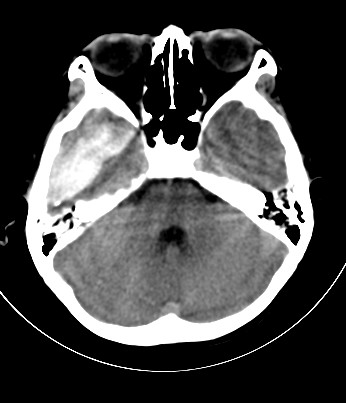

外伤一天,m,21y,骨窗示右颞骨骨折.

请大家看看,是脑内还是脑外(硬膜下还是硬膜外).请说说理由.谢谢.

右侧颞叶大片状形态不规则高密度影,边缘较模糊,无明显白质挤压移位。支持脑错裂伤、脑内血肿。

右侧颞叶大片状形态不规则高密度影,内缘较模糊,外缘紧贴颅板,无明显白质挤压移位伤。

依据:1.右侧颞叶不规则形血肿密度影,周围有水肿;

2.有明显占位效应;

3.颅板下硬膜下间隙存在。

脑内脑外全有,上方比较局限近似梭形改变,考虑硬膜外血肿。没有跨过颅缝,且是脑膜中动脉所在的位置。中线移位,占位效应明显。后方条带状增高影,周围有水肿带,考虑脑内血肿。

右颞区硬膜外血肿伴右颞叶脑挫裂伤,依据

1出血灶局限,硬膜下出血广泛

2边缘光滑,硬膜下出血边缘不清楚

3出血合并骨折,硬膜下出血合并骨折的少

4在外伤的同侧,硬膜下出血可以在同侧,也可以在对侧

右颞叶见混杂密度灶(以高密度灶为主)右侧脑室受压变形,中线结构左移,右颞部颅骨内板下见弧形高密度灶,右侧裂池及部分脑沟内见高密度灶;

结论:1:右颞叶脑挫裂伤;

2:右侧硬膜下血肿;

3:蛛网膜下腔出血。